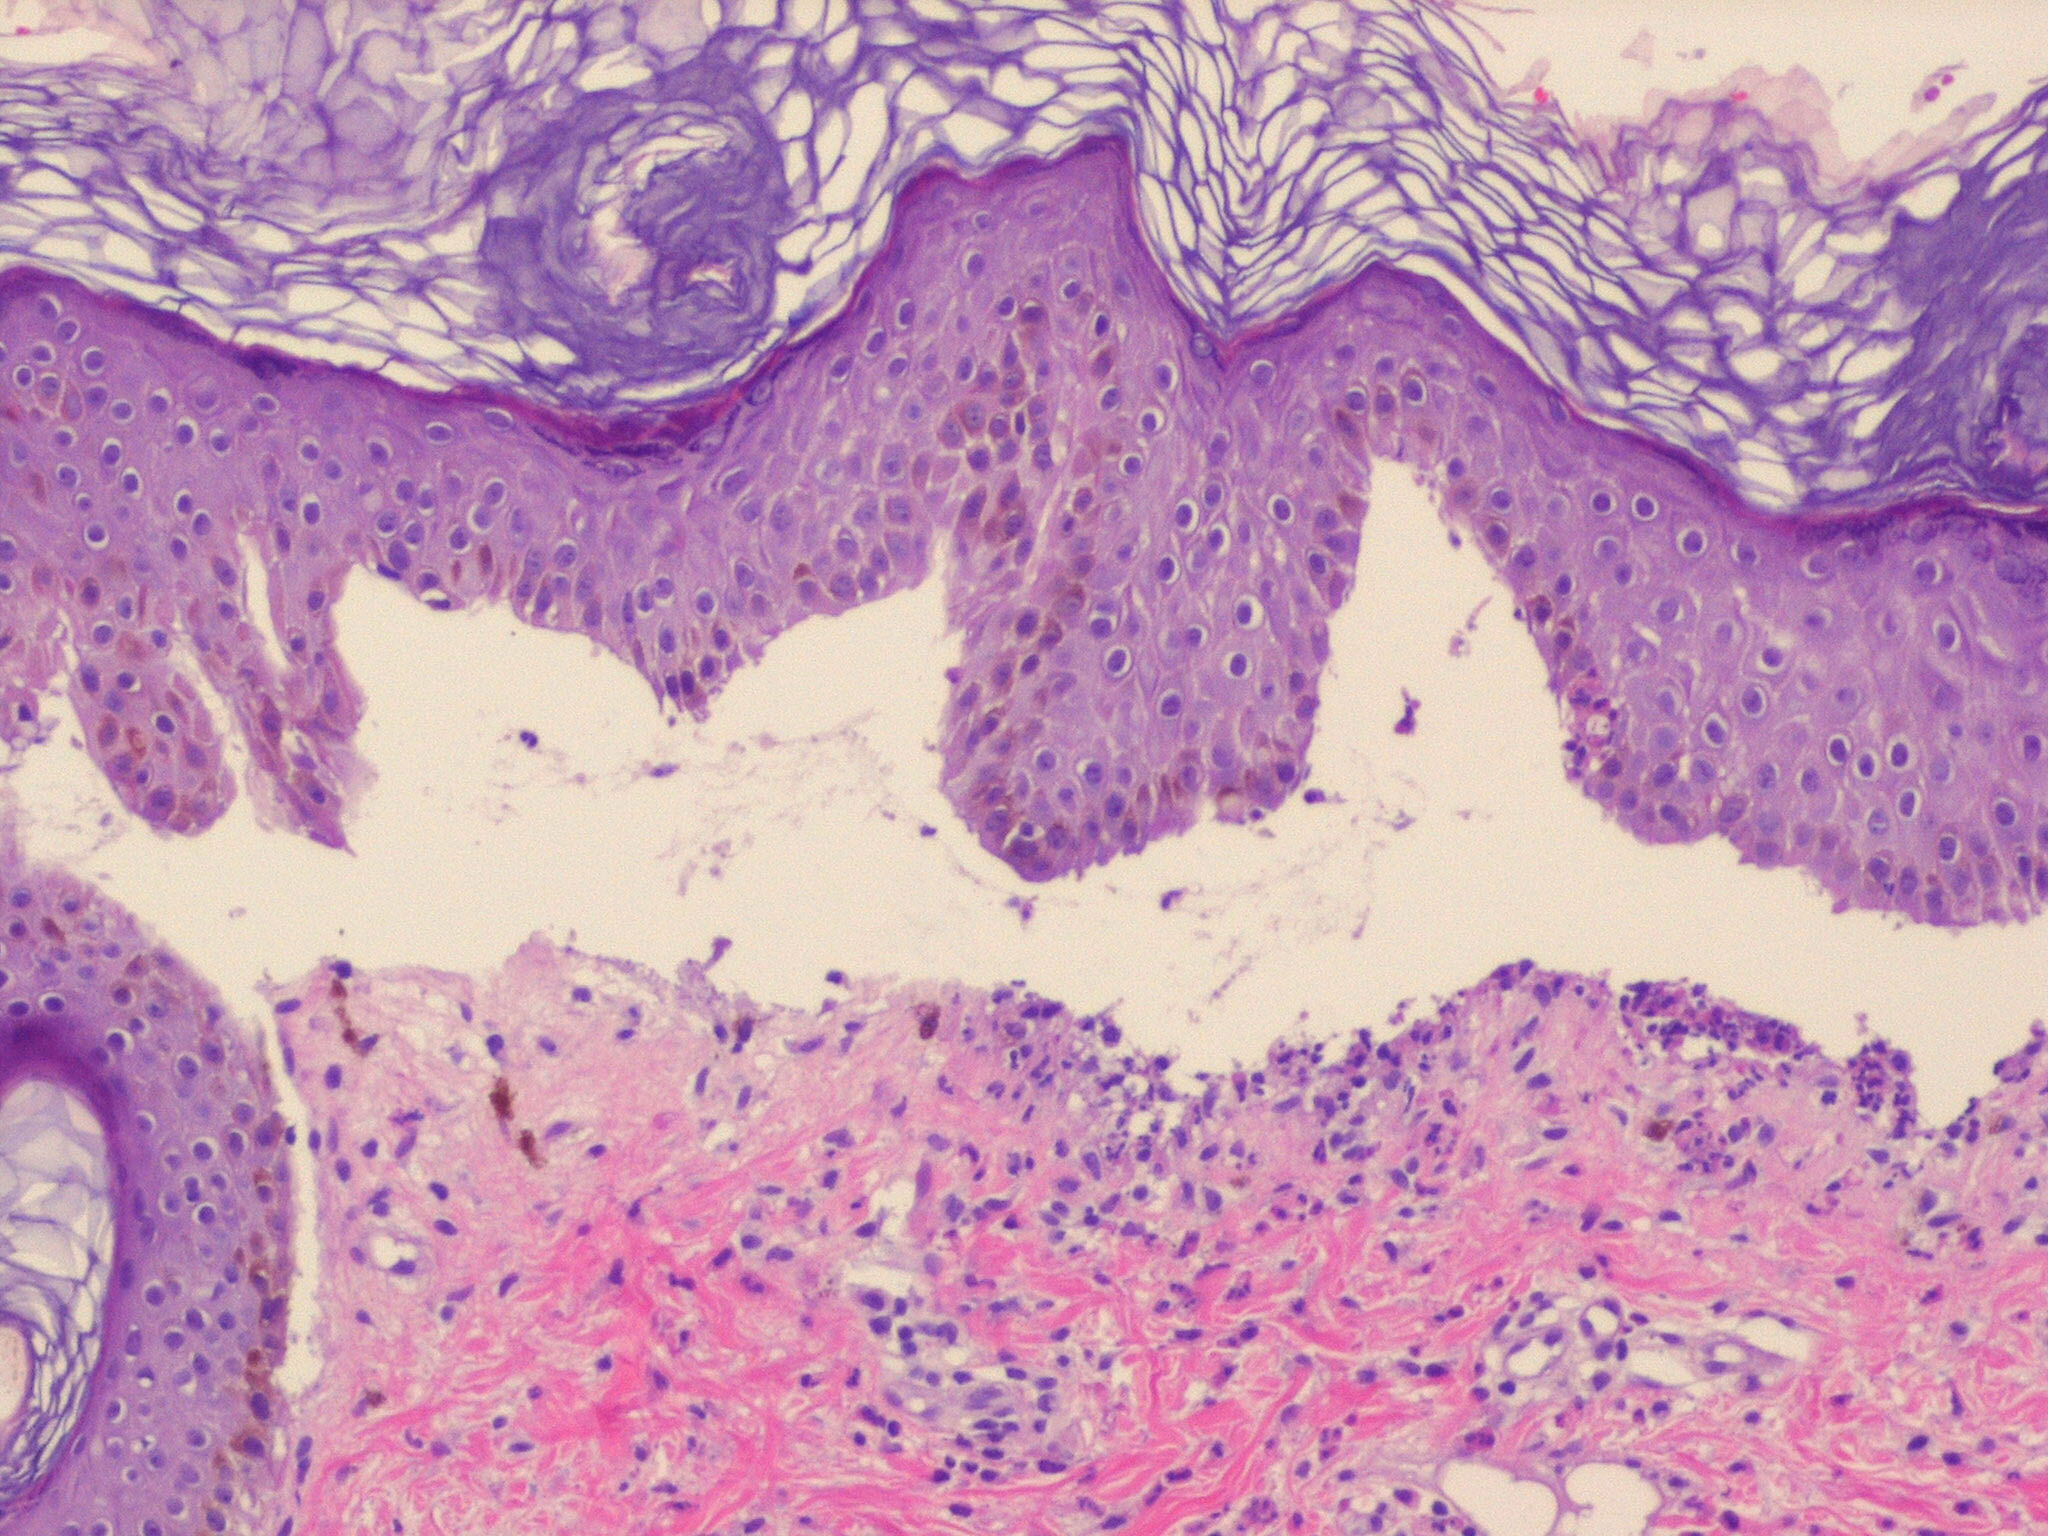

Histologically, the lesions of bullous impetigo show vesicle formation in the sub-corneal or granular region, occasional acantholytic cells within the blister, spongiosis, edema of the papillary dermis, and a mixed infiltrate of lymphocytes and neutrophils around blood vessels of the superficial plexus.